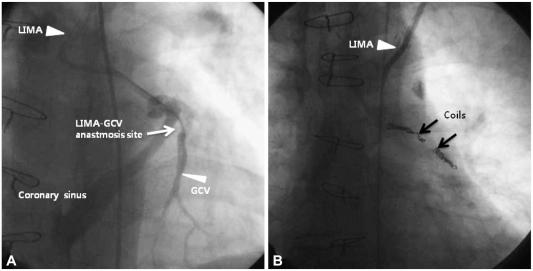

Iatrogenic left internal mammary artery to great cardiac vein anastomosis treated with coil embolization.

Inadvertent left internal mammary artery (LIMA)-great cardiac vein (GCV) anastomosis is a rare complication of coronary artery bypass graft surgery. Patients with iatrogenic aortocoronary fistula (ACF) were usually treated surgical repair, percutaneous embolic occlusion with coil or balloon. We report a case of iatrogenic LIMA to GCV anastomosis successfully treated with coil embolization and protected left main coronary intervention through the percutaneous transfemoral approach.